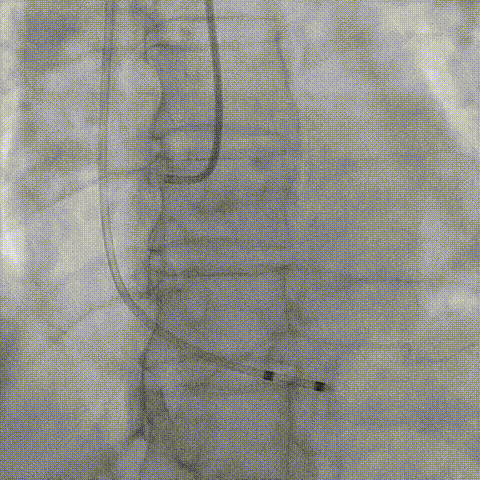

主动脉

右股

左股